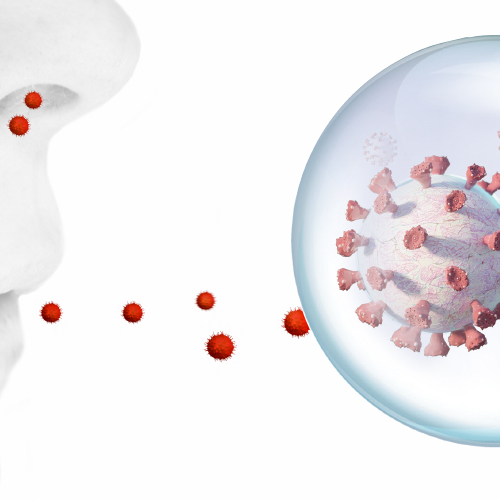

Aerosol Awareness: The Next Stage in Optimal Protection

As new research expands the evidence on potential pathways of infection, the dental industry is becoming more aware of how to mitigate aerosols throughout the practice. This eBook details the latest in preventive techniques and advanced equipment designs to create the safest working environment.